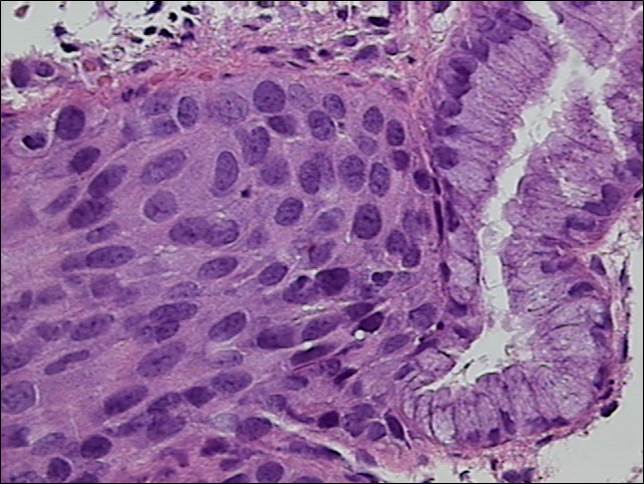

Histología

Por medio de técnicas morfológicas, buscamos las causas, desarrollo y consecuencias de las enfermedades. La relación de los tejidos desde un punto de vista mínimo, es concerniente para la medicina y el estudio morfológico del cuerpo, para la resolución de enfermedades.